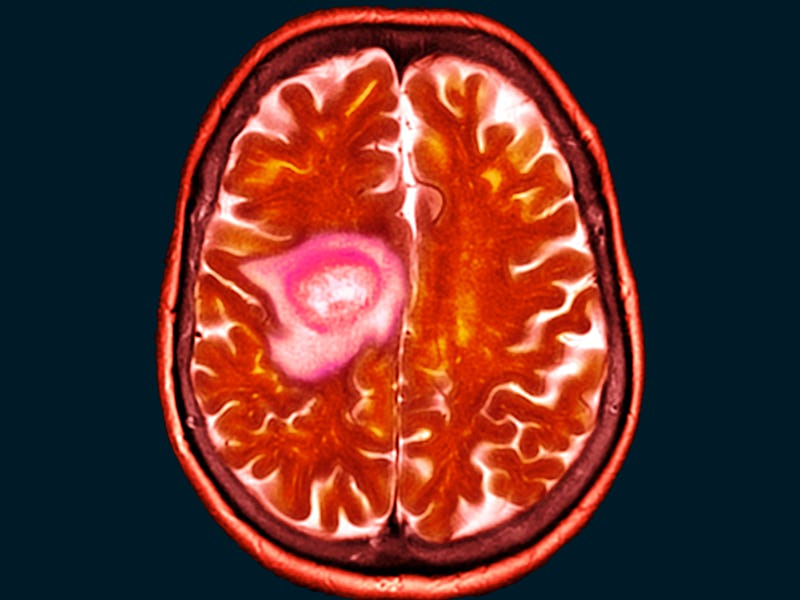

Glioblastoma is the most commonly diagnosed – and most lethal – kind of malignant brain tumor. Surgery, radiation, and chemotherapy can help slow their growth, but the tumor almost always returns. Roughly 18,000 people in the United States receive a diagnosis of glioblastoma every year; the median survival prognosis is less than fifteen months.

Why glioblastoma is so aggressive — What makes glioblastoma so good at resisting treatment is thought to be attributable to a subpopulation of cells, called brain tumor-initiating cells, or BTICs. These cells possess “stem cell-like” properties, and are extremely adept at regrowing.